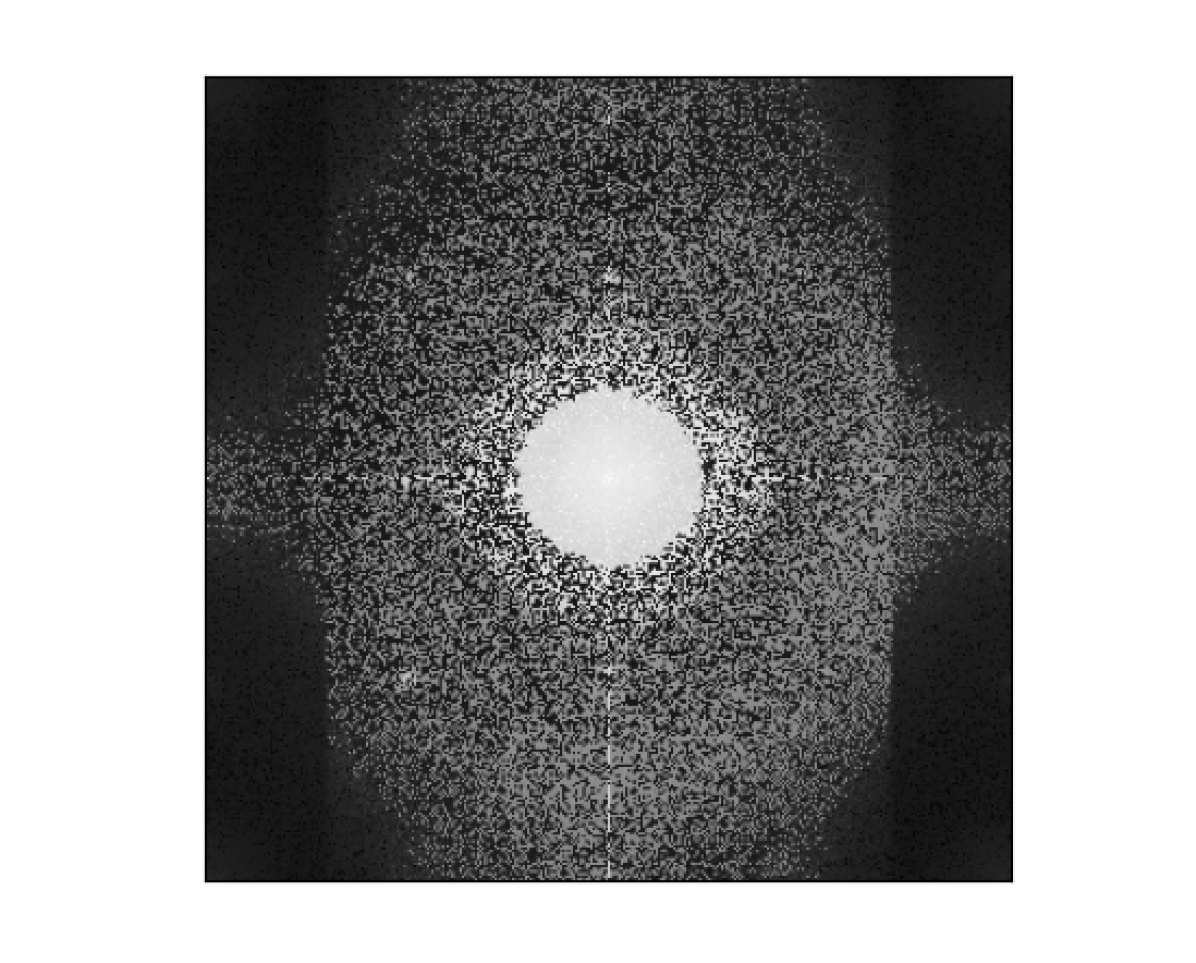

In this section we briefly present the densities and trajectories for various methods of estimating the target sampling densities as described in Sec. II-C. Then we briefly go through the retrospective reconstruction results that we obtained.

III-A Densities and trajectories

The varied target sampling densities and their respective SPARKLING trajectories are presented in Fig. 1. We see that the direct spectrum-based density 𝝆sbsubscript𝝆𝑠𝑏\boldsymbol{\rm\rho}_{sb} is extremely dense at the center of k-space, leading to really dense sampling here in the respective trajectories. The log-spectrum method does indeed flatten out the density 𝝆lsbsubscript𝝆𝑙𝑠𝑏\boldsymbol{\rm\rho}_{lsb}, allowing the trajectories to explore more high frequencies. Finally, the LOUPE based density does oversample the center of k-space resulting in a scheme very similar to variable density sampling. However, the density 𝝆lbsubscript𝝆𝑙𝑏\boldsymbol{\rm\rho}_{lb} from LOUPE is more grainy since the learning of this density happens on a Cartesian grid.

Figure 1: (A): The target sampling densities obtained for T1subscriptT1\text{T}_{1}-weighted images with: (i) VDS (𝝆vdssubscript𝝆𝑣𝑑𝑠\boldsymbol{\rm\rho}_{vds}), a radially decaying parameterized density, with C=25% and D=2 in [11]; (ii) Average spectrum (𝝆sbsubscript𝝆𝑠𝑏\boldsymbol{\rm\rho}_{sb}) over the dataset based on [12]; (iii) Average logarithm of the spectrum (𝝆lsbsubscript𝝆𝑙𝑠𝑏\boldsymbol{\rm\rho}_{lsb}) over the dataset, to flatten the density in (ii); (iv) LOUPE (𝝆lbsubscript𝝆𝑙𝑏\boldsymbol{\rm\rho}_{lb}) [17] coupled with XPDNet [24] reconstruction.  (B): Corresponding k-space trajectories generated with Nc=16subscript𝑁𝑐16N_{c}=16 (R=2.5𝑅2.5R=2.5), Ns=512subscript𝑁𝑠512N_{s}=512, Gmax=40subscript𝐺max40G_{\rm max}=40 mT/m and Smax=180subscript𝑆max180S_{\rm max}=180 T/m/s. For illustration purpose, a single shot is colored in red.